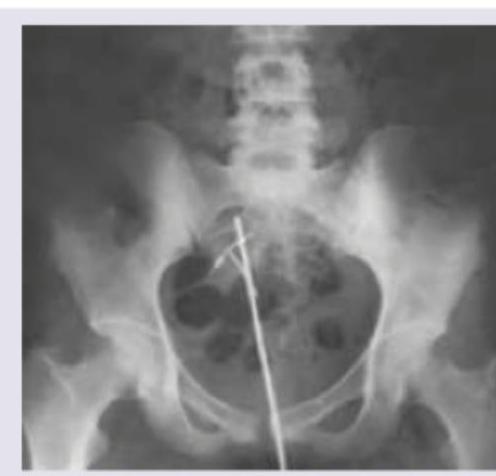

The X-ray pelvis AP shows presence of:

Explanation: ***Uterine sounding to check position of dislodged IUD*** - The image shows a **T-shaped radiopaque object**, consistent with an **intrauterine device (IUD)**, located aberrantly outside the expected uterine cavity but within the pelvis. - A **uterine sound**, appearing as a long, thin radiopaque rod, has been inserted, indicating an attempt to locate or assess the position of the dislodged IUD. *Endoscopic removal of ureteric stones* - This image does not show any typical features of **ureteric stones** (e.g., small, dense calcifications along the ureteric course) or instruments commonly used for their endoscopic removal (e.g., ureteroscope or basket catheter). - The depicted objects are clearly a dislodged IUD and a uterine sound, which are unrelated to ureteric stone removal. *Uterine sounding to check for the site of uterine tear* - While a **uterine sound** can be used in cases of uterine perforation, the primary finding here is a clearly **dislodged IUD** outside the uterus. - The presence of the IUD in an extra-uterine location, rather than an obvious tear, suggests the sounding is for IUD localization. *Pelvic trauma* - There are **no signs of bony fractures, dislocations, or soft tissue injury** consistent with **pelvic trauma** on this X-ray. - The radiopaque objects observed are medical devices (IUD and uterine sound), not indicative of traumatic injury.